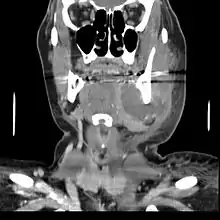

If left untreated, a severe tooth abscess may become large enough to perforate bone and extend into the soft tissue eventually becoming osteomyelitis and cellulitis respectively. From there it follows the path of least resistance and may spread either internally or externally. The path of the infection is influenced by such things as the location of the infected tooth and the thickness of the bone, muscle and fascia attachments.

External drainage may begin as a boil which bursts allowing pus drainage from the abscess, intraorally (usually through the gum) or extraorally. Chronic drainage will allow an epithelial lining to form in this communication to form a pus draining canal (fistula).[4] Sometimes this type of drainage will immediately relieve some of the painful symptoms associated with the pressure.

Internal drainage is of more concern as growing infection makes space within the tissues surrounding the infection. Severe complications requiring immediate hospitalization include Ludwig's angina, which is a combination of growing infection and cellulitis which closes the airway space causing suffocation in extreme cases. Also infection can spread down the tissue spaces to the mediastinum which has significant consequences on the vital organs such as the heart. Another complication, usually from upper teeth, is a risk of sepsis traveling through pathways to which it can possibly lead to endocarditis, brain abscess (extremely rare), or meningitis (also rare).